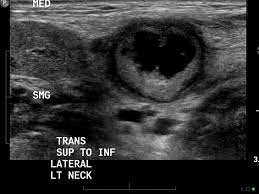

The person operating the ultrasound will sweep, or fan, the probe back and forth to look at different areas in 90 degree angle images. In addition, the following tests may be used to diagnose head and neck cancer: Cancerous lymph nodes can occur anywhere on the neck and are typically described as firm, painless, and sometimes may be immovable. In the normal neck, about 90% of nodes with a maximum transverse diameter greater than 5 mm will demonstrate an echogenic hilus on high resolution ultrasound. Symptoms of head and neck cancer can include:

Air and bone also reflect sound waves. A lump in the neck —cancers that begin in the head or neck usually spread to lymph nodes in the neck before they spread elsewhere. A neck ultrasound may help diagnose (find): Breast ultrasound images are seen from superficial (skin) to deep (chest wall muscle) over a segment of tissue. A neck ultrasound can be used to observe the thyroid gland to look for nodules, growths, or tumors. But now i am worried that the reason the lump didn't show on the ultrasound is because it is actually under the skin in my neck (i.e in my throat) rather than on my actual thyroid/neck. David dang answered 14 years experience radiology node, cyst or others: A small lump on the neck usually is a lymph node, a small sebaceous cyst or a lipoma, although it could be something else. The most common symptom of thyroid cancer is a hard lump on the neck—but most patients experience no symptoms at all. This means that they are larger than about 1 centimeter (about 1/2 inch) across. Optimal positioning and exposure of the neck for ultrasound of the thyroid and parathyroid glands (a, b) and lateral neck for lymph node examination and mapping (c).while the vast majority of patients are supine on the exam table with a pillow supporting the shoulders to allow gentle neck extension, keep in mind that some patients have beautiful anatomy (d) that allows ultrasound exam even in. 1), and the presence of an echogenic hilus within lymph nodes was previously considered a sign of benignity. What does a healthy kidney look like on an ultrasound?

A small device called a transducer is moved over the area. Optimal positioning and exposure of the neck for ultrasound of the thyroid and parathyroid glands (a, b) and lateral neck for lymph node examination and mapping (c).while the vast majority of patients are supine on the exam table with a pillow supporting the shoulders to allow gentle neck extension, keep in mind that some patients have beautiful anatomy (d) that allows ultrasound exam even in. The camera remains attached either to a flexible tube called endoscope or to a probe, while it passes within an opening in your body, often your mouth. In the normal neck, about 90% of nodes with a maximum transverse diameter greater than 5 mm will demonstrate an echogenic hilus on high resolution ultrasound. Ultrasound an ultrasound is sometimes used, especially to look at the thyroid, salivary glands and lymph glands in the neck. A neck lump or nodule is the most common symptom of thyroid cancer. Should your doctor suggest that you undergo a neck ultrasound, you can be confident that your scan will be conducted by highly trained, experienced and caring sonographers. But now i am worried that the reason the lump didn't show on the ultrasound is because it is actually under the skin in my neck (i.e in my throat) rather than on my actual thyroid/neck.

If a biopsy is needed, doctors use ultrasound to scan the area again, ensuring that they know exactly where to place the needle. In addition, the following tests may be used to diagnose head and neck cancer: And my neck look like an old shapai. A lump will form when a cancer cell infiltrates the capsule and multiplies. These are frequently seen in nodules containing papillary thyroid cancer. But ultrasound is usually the first choice for looking at the thyroid and neck structures. The normal neck contains scores of lymph nodes some of which are easily seen with ultrasound. Ultrasound an ultrasound is sometimes used, especially to look at the thyroid, salivary glands and lymph glands in the neck.